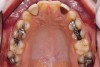

Fig 13. Prosthetic phase completion. Maxillary occlusal view. Note arch form change without compromise to the buccal alveolar bone and periodontal phenotype.

Figure 13